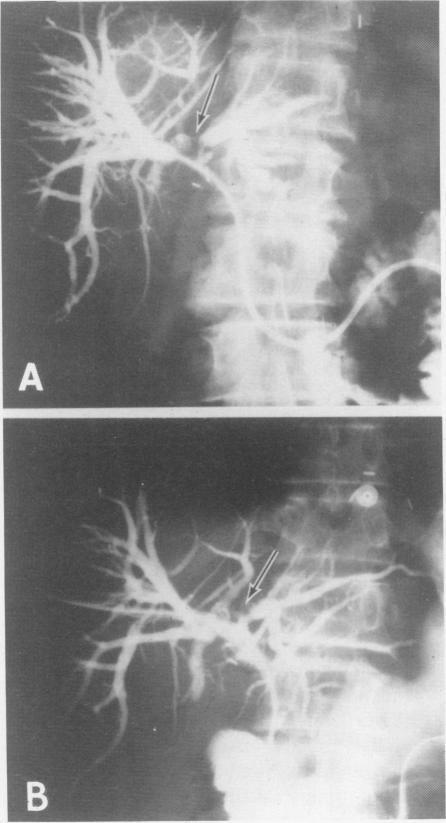

Current laser applications in general surgery.

Ann Surg. 1988 Apr;207(4):355-72. doi: 10.1097/00000658-198804000-00001.